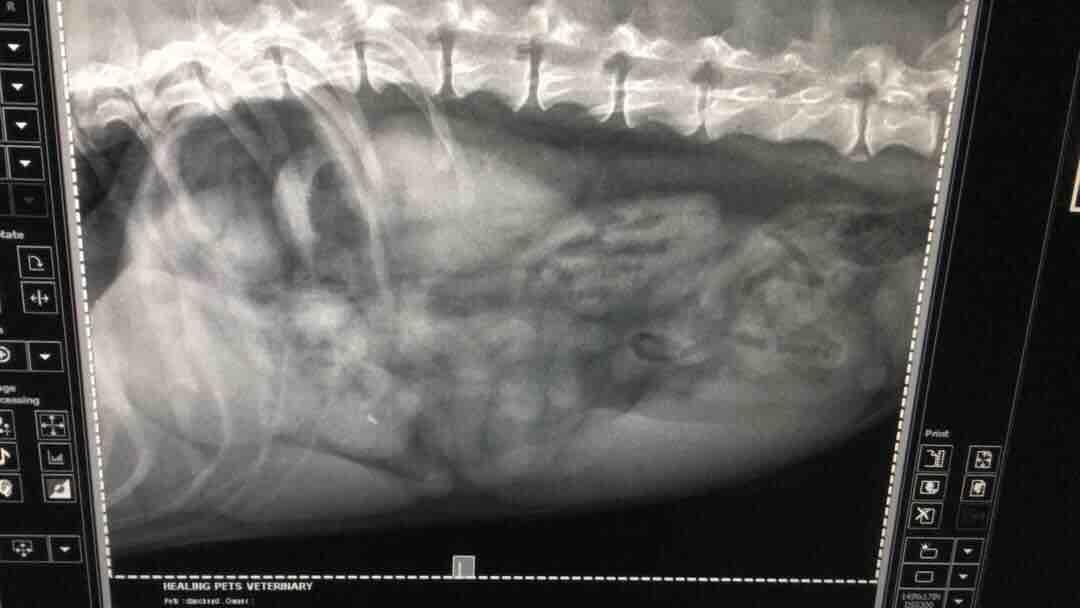

Pet's info: Dog | Dachshund | Male | neutered | 8 years and 1 month old | 25 lbs

My boy has got some identified foreign object in his stomach shown in the X-ray but he isn't acting sick not vomiting but still active and eating well. However he has been on diarrhea soft poop with jelly red blood like on the stool for the past 6 days. My question is, 1. how long can I wait before we can do any indepth diagnostic or even operation to remove object in his stomach if he isn't acting sick? Can we wait a week or two? 2. Does the objects look like tumor to you? 3.

Hi there and thank you for using pet coach to address your concern. The soo we the foreign material is taken out of the stomach the better. I know it is not causing a problem now but if it decides to pass through into the intestines, this could cause far worse problems than just sitting in the stomach. I would advise against waiting so thst you are not faced with an emergency surgery. If the object passes into the intestines, it could cause a lot of trauma which may lead to part of the intestines dying due to lack of circulation from squeezing on this object. It is difficult to say if this is soft tissue or not but it has the characteristic of an ingested foreign object. I hope this helps guide you in the right direction. Please let me know if you have any other questions or concerns.